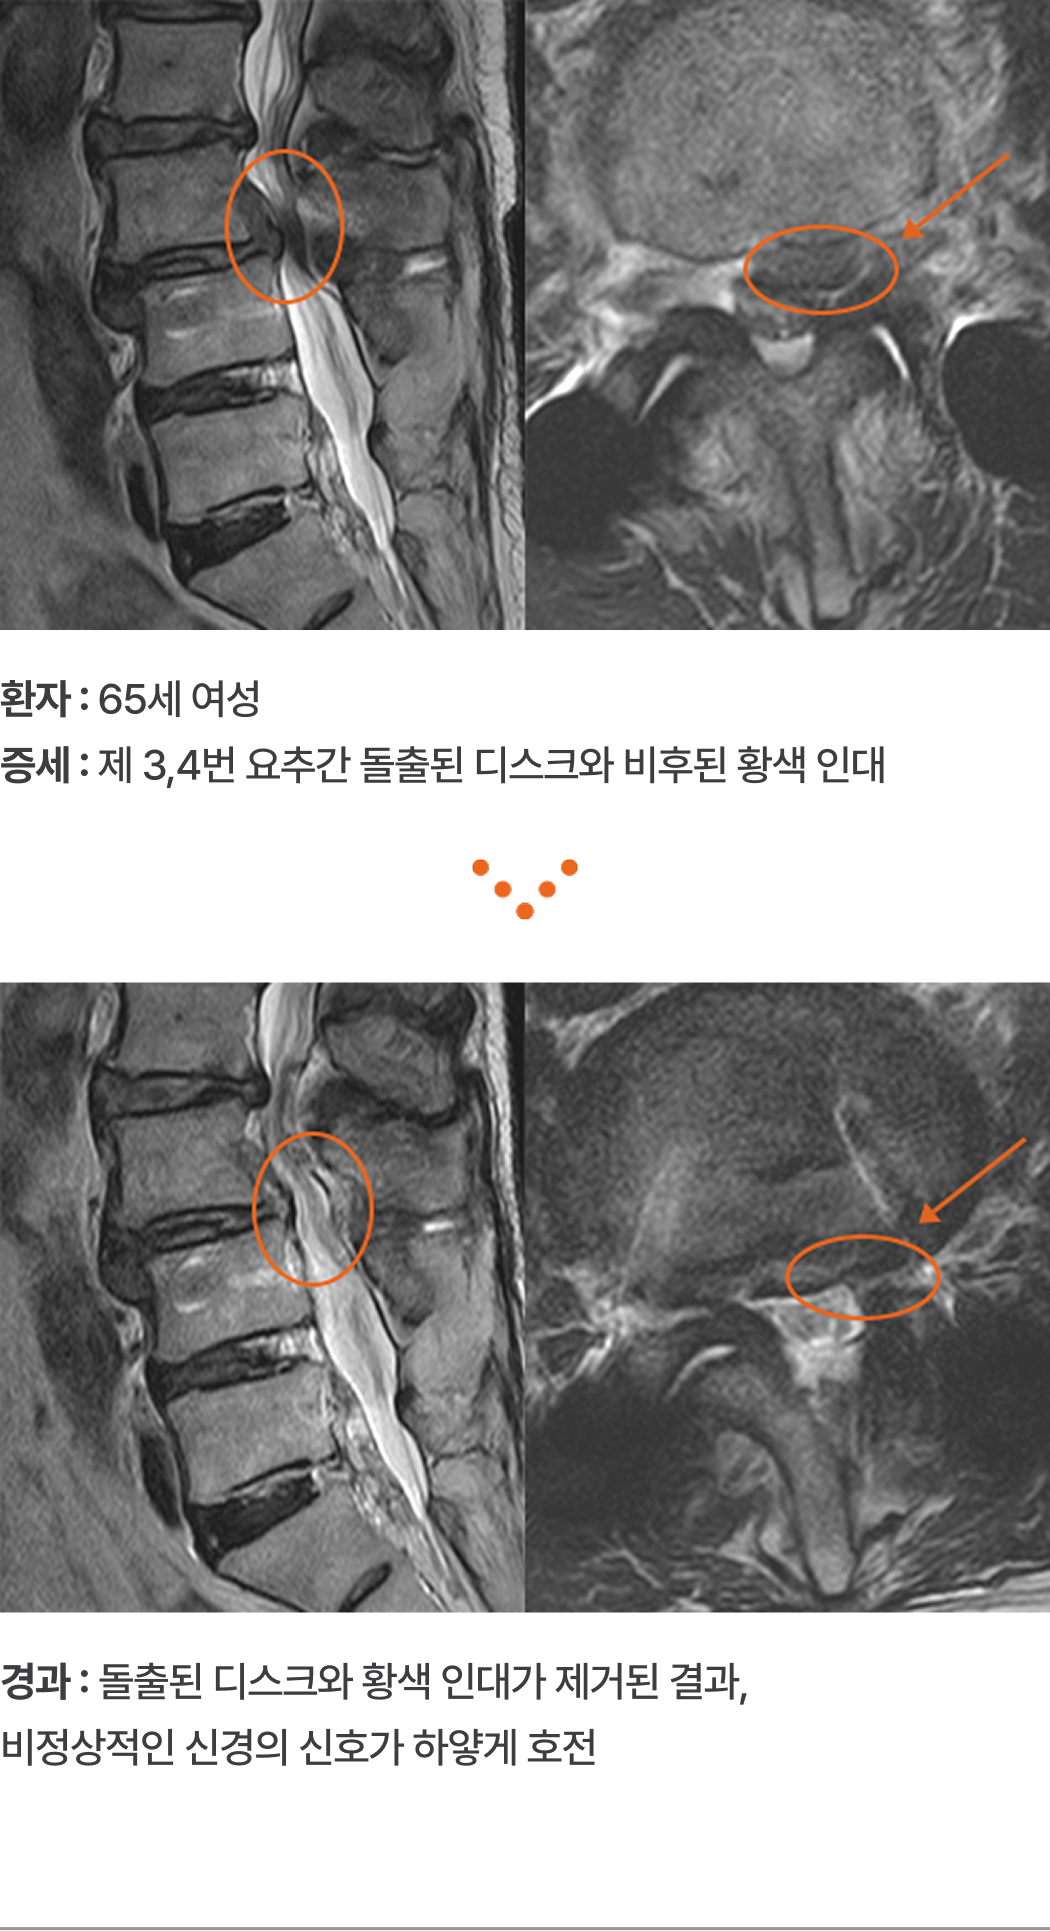

환자 :

65세 여성

증세 :

제 3,4번 요추간 돌출된 디스크와 비후된 황색 인대

경과 :

돌출된 디스크와 황색 인대가 제거된 결과, 비정상적인 신경의

신호가 하얗게 호전